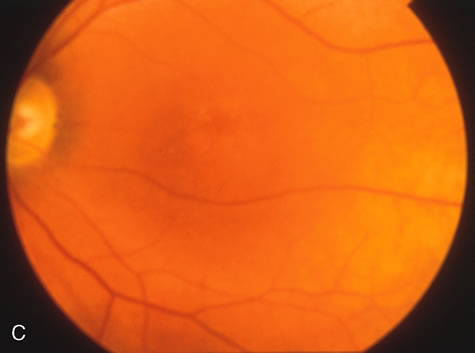

Of more clinical importance is the role of FA in the diagnosis and treatment of cystoid macular edema (CME) (Fig. 1C and D). Stereoscopic FA indicates that the leakage, which may be diffuse or have the typical petaloid stellate appearance of CME, can come from the perifoveal retinal capillaries, from the choroid through the RPE, or from a combination of both sources.4 With the recent suggestion that CME in RP may be successfully treated with acetazolamide,5, 6 FA is thus important to document the diagnosis of CME, establish the origin(s) of leakage, and follow patients during and after therapy.